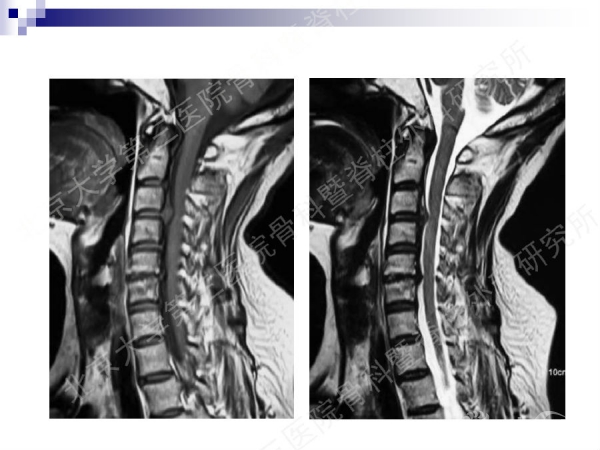

今天,在北京大学第三医院骨科暨脊柱外科研究所刘忠军教授分享的《颈椎人工椎间盘置换手术注意问题》课件中,他将通过大量影像资料、临床研究数据和长期随访结果,给大家介绍现阶段最重要的颈椎非融合技术——人工椎间盘置换术的适应证、禁忌证和其他需要密切注意的一些问题,提醒同道关注与手术技术及内植物相关的尺寸、终板顺列、中心轴线顺列等问题,严格把控手术指征,规范、精准地开展颈椎人工椎间盘置换手术,保障手术疗效。